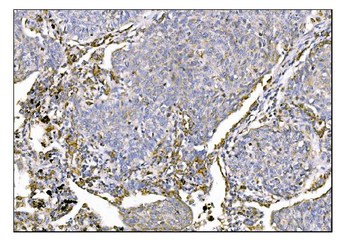

IHC staining of FFPE human colon carcinoma with MerTK antibody (clone TPKR-1). HIER: boil tissue sections in pH9 10mM Tris with 1mM EDTA for 10-20 min and allow to cool before testing.